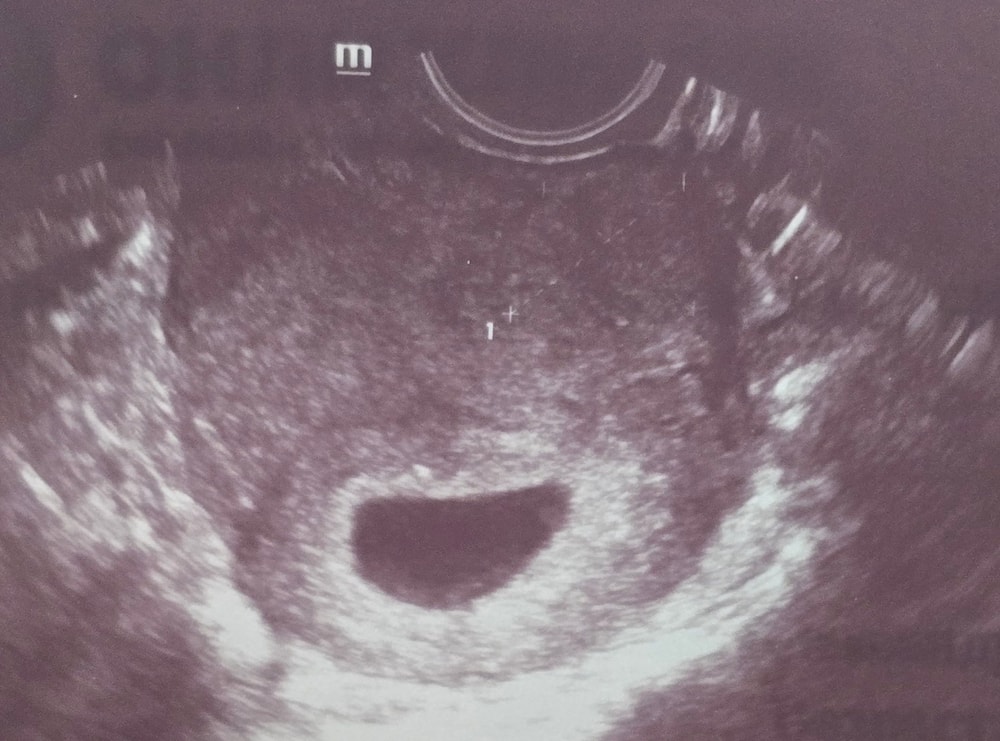

Результаты: УЗИ, КТГ, доплера, скринингаДевочки, скажите пожалуйста похоже ли это на миому? Может тут есть врачи узи🌸

Недавно я проходила УЗИ несколько раз, и результаты были разными:

- На одном УЗИ плодное яйцо было очень маленьким,миомы не обнаружили.

- На следующем УЗИ в другой клинике я рассказала врачу об операции и попросила посмотреть рубец. Она сообщила, что на этом же месте, где была операция, обнаружена миома размером 23×20 мм.

- Через пять дней я сделала УЗИ у другого врача на другом аппарате. Он смотрел очень долго, около 25 минут, и не увидел никакой миомы. Врач сказал, что может не заметить миому, если она очень маленькая, но я уверена, что на предыдущем УЗИ она была 23×20 мм. Врач также посмотрел предыдущий снимок УЗИ и сказал, что он очень сомнительный.